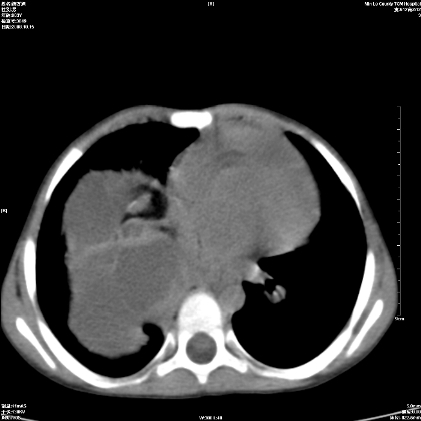

标题: PED1609:男性,3岁。彩超示肝Ca. [打印本页]

标题: PED1609:男性,3岁。彩超示肝Ca.

考虑后纵隔恶性畸胎瘤伴肝内多发转移可能性大,右侧肾上腺转移不除外.

3岁;肝低密度灶;有钙化;有转移灶;考虑肝母细胞瘤;查afp

考虑神经母细胞瘤并肝转移

考虑:1、右侧后下纵隔畸胎瘤。

2、肝脏多发血管内皮细胞瘤。

建议:增强确诊。